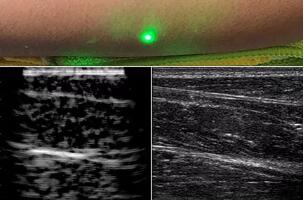

目前,研究人員已經(jīng)與健康的志愿者測(cè)試了他們的系統(tǒng):從半米遠(yuǎn)處掃描了他們的前臂,并將這些結(jié)果與傳統(tǒng)超聲的結(jié)果進(jìn)行了比較。他們能夠觀察到深達(dá)6厘米的組織,并能看到肌肉,脂肪和骨頭,并報(bào)告其結(jié)果可與標(biāo)準(zhǔn)超聲相媲美。

研究人員用一種激光裝置測(cè)試了這個(gè)想法,該裝置使用一個(gè)波長(zhǎng)為1,550納米的脈沖激光來(lái)產(chǎn)生聲波,并使用第二個(gè)連續(xù)激光,調(diào)諧到相同的波長(zhǎng)以遠(yuǎn)程檢測(cè)反射的聲波。第二個(gè)激光器是靈敏的運(yùn)動(dòng)檢測(cè)器,可測(cè)量聲波從肌肉,脂肪和其他組織反射回來(lái)而引起的皮膚表面振動(dòng)。反射的聲波產(chǎn)生的皮膚表面運(yùn)動(dòng)會(huì)導(dǎo)致激光頻率發(fā)生變化,這種變化可以測(cè)量。通過(guò)機(jī)械掃描人體上的激光,科學(xué)家可以獲取不同位置的數(shù)據(jù)并生成該區(qū)域的圖像。